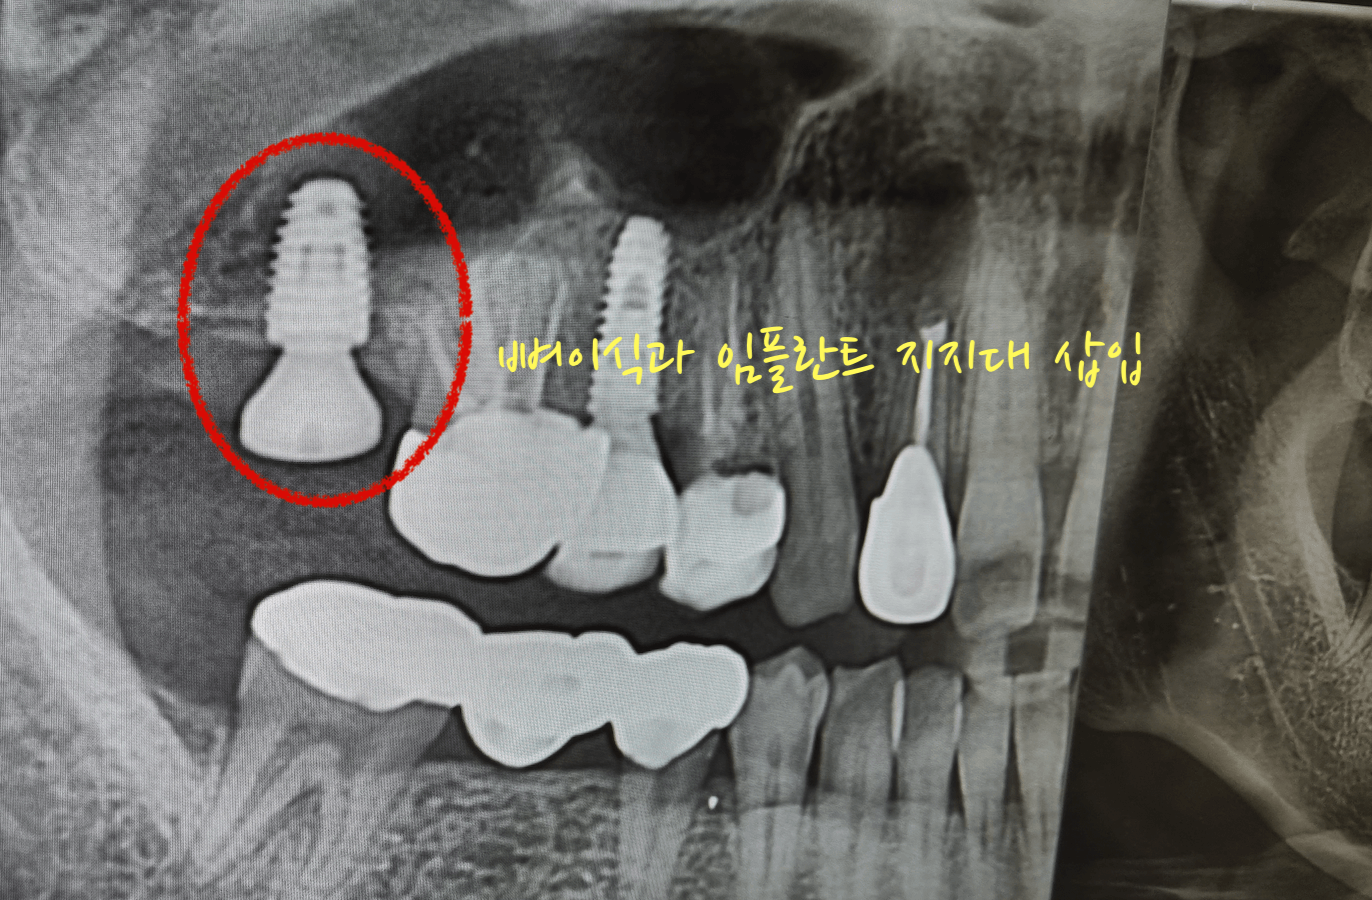

어금니 맨안쪽 치아를 염증 때문에 발치하고 3개월 뒤 어느 정도 뼈가 아물고, 오늘 해당 어금니 부분에 뼈이식과 임플란트 지지대를 삽입하고 왔습니다. 이것까지 하고 나서 치조골 이식한 것과 임플란트가 잘 아물면 그 이후 보철을 씌우면 됩니다.

간단히 말해서 신경치료 다끝난후 크라운을 씌우듯 뼈이식한 임플란트가 잘 고정된 다음 보철을 씌어 마무리를 하게 됩니다. 대략 또 몇 달 정도 기다린 후 보철을 씌어 마무리하면 임플란트 수술은 완전히 끝나게 됩니다.

임플란트 삽입과 뼈이식 더하기 상악동거상술까지 진행하여 끝난 시간은 치과 수술실 이동후 대략 30분도 안 걸린 듯합니다. 수술 후 거즈를 30분 정도 물고 있으라고 했는데, 집에 와서 거즈를 빼니깐 피도 거이 하나도 묻어 있지 않았습니다.

이번 포스팅의 사진 또한 저의 치아 상태 사진 입니다. 그러니 불법으로 퍼가지 마세요, 부끄럽습니다. 대부분의 치아가 크라운을 씌우거나 임플란트를 해놓은거라 부끄럽네요. 대신 이모든것들이 직접 경험한 내용이기에 팩트는 확실히 전달 될것 같습니다. 아래 포스팅 또한 제가 모두 경험한 내용이니 참고하세요.